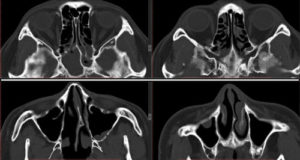

- информативнее других методов обнаруживают сфеноидит компьютерная или магнитно-резонансная томография;

КТ — исследование пазухи с помощью рентгеновского излучения. КТ позволяет выявить аномалии синуса, степень поражения слизистой. При исследовании с помощью КТ определяется уровень гноя в пазухе.

Ещё более информативным методом диагностики является МРТ — она выявляет послойные поражения, которые могут быть не замечены на КТ.